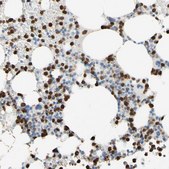

immunohistochemistry: 1:50- 1:200

All Prestige Antibodies Powered by Atlas Antibodies are developed and validated by the Human Protein Atlas (HPA) project and as a result, are supported by the most extensive characterization in the industry.

The Human Protein Atlas project can be subdivided into three efforts: Human Tissue Atlas, Cancer Atlas, and Human Cell Atlas. The antibodies that have been generated in support of the Tissue and Cancer Atlas projects have been tested by immunohistochemistry against hundreds of normal and disease tissues and through the recent efforts of the Human Cell Atlas project, many have been characterized by immunofluorescence to map the human proteome not only at the tissue level but now at the subcellular level. These images and the collection of this vast data set can be viewed on the Human Protein Atlas (HPA) site by clicking on the Image Gallery link. We also provide Prestige Antibodies® protocols and other useful information.

• IHC tissue array of 44 normal human tissues and 20 of the most common cancer type tissues.